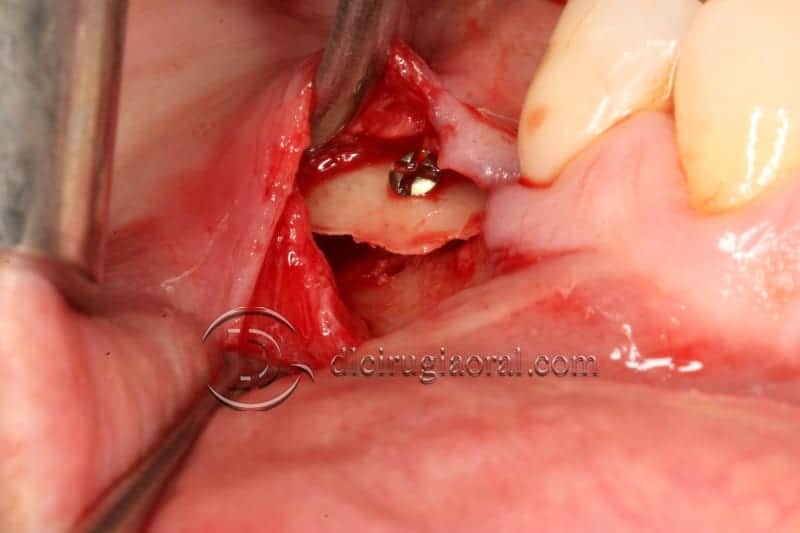

A bone block is harvested from the retromolar area and then split into two very thin bone blades. These blades will be used to restore the missing cortical walls.

Autogenous from chips, obtained with a safe-scrapper like this one, and a bone crusher, will be placed in the space created by those two thin bone blades.

The whole procedure is performed, if possible, through the already explained tunnel approach.